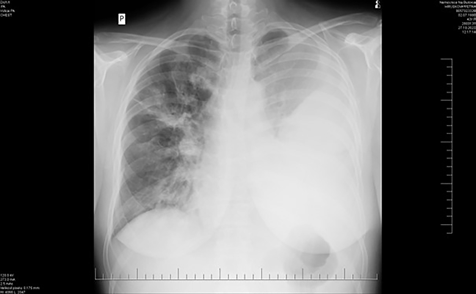

Obr. 1 Zánětlivý infiltrát v levé polovině hrudníku s fluidothoraxem, menší rozsah nálezu vpravo.Vstupní laboratorní hodnoty po přijetí byly následující: krevní obraz bez leukocytózy, ale s výraznou neutrofilií, 36 % neutrofilních tyčí, NLR (neutro/lymfo counts ratio) 18,5, C‑reaktivní protein (CRP) 360 mg/l, prokalcitonin (PCT) 4,9 mg/l, lehká elevace transamináz, GGT (gama‑glutamyltransferáza) 6,72 μkat/l, proto byly odebrány vzorky k sérologické diagnostice hepatitidy. V klinickém obraze však dominovala dušnost a hyposaturace při pozitivní DD (zvýšené hladině D‑dimerů). Následně bylo doplněno vyšetření pomocí CT angiografie plic, kde byl sice doložen nález bez známek plicní embolizace, byla však popsána zánětlivá konsolidace větší části levého dolního laloku, prchavé infiltráty i v centrální části všech laloků pravé plíce a levostranný fluidothorax. Z laboratoře byl hlášen slabě pozitivní pneumokokový antigen v moči, pacientka byla zajištěna empiricky ampicilinem s doxycyklinem. Z pěti lahviček hemokultur byl vykultivován Streptococcus pneumoniae, doxycyklin byl tudíž vysazen, antibiotická léčba byla deeskalována na krystalický peniclin G. PCR test výtěrem z nosohltanu opět potvrdil pozitivní Str. pneumoniae. Na zvolené terapii se klinický stav zlepšuje, průtoky kyslíku se snižují. V kontrolní laboratoři byla nově zjištěna výrazná leukocytóza s neutrofilií, hodnoty zánětlivých parametrů sice v poklesu – CRP 257,8 mg/l, PCT v normě, ale došlo ke zhoršení dušnosti a bolestí levé poloviny hrudníku. Rtg plic ze dne 27. října 2023 – zastření celého levého hemithoraxu – progrese výpotku (obr. 1); 28. října – zhoršení dušnosti. Zamýšlená hrudní drenáž pod ultrasonografickou kontrolou nebyla vzhledem k septaci výpotku provedena. Doplněno vyšetření výpočetní tomografií (CT) hrudníku s nálezem rozsáhlých septovaných tekutinových kolekcí (obr. 2) – po dohodě s pneumologem a chirurgem byla pacientka indikována k drenáži hrudním chirurgem. Do terapie byl přidán linezolid*. Dne 30. října byl pod sonografickou kontrolou zaveden hrudní drén v cca 6./7. mezižebří ve střední axilární čáře vlevo, drén odvedl žlutavou lehce kalnou tekutinu, celkem cca 1 500 ml, dne 31. října si pacientka drén zrušila; 31. října bylo provedeno kontrolní sonografické vyšetření hrudníku – laterálně v místě drénu lem tekutiny v podkoží, atelektatická plíce, bazálně z dorzální strany nad bránicí 20–30 mm lemu tekutiny, max. paravertebrálně, fibrinová vlákna.